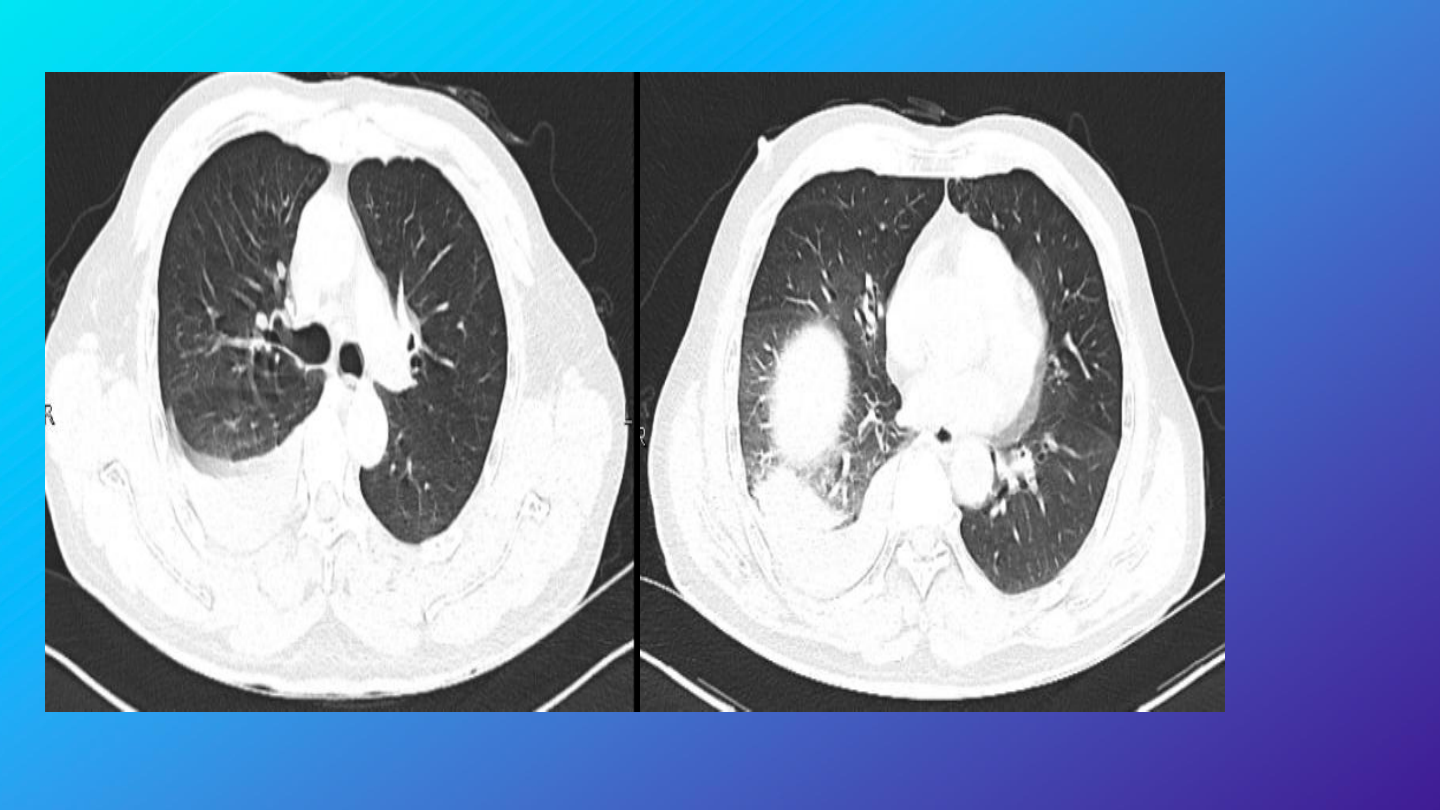

完善胸部增强

右侧胸腔积液、积血,较前片

2024-10-22 10:20

)积液、积血

增多,请结合临床;

右肺下叶肺不张,右肺各叶及左

肺下叶炎性渗出改变。

右侧第

5

6

前肋骨皮质略褶皱。